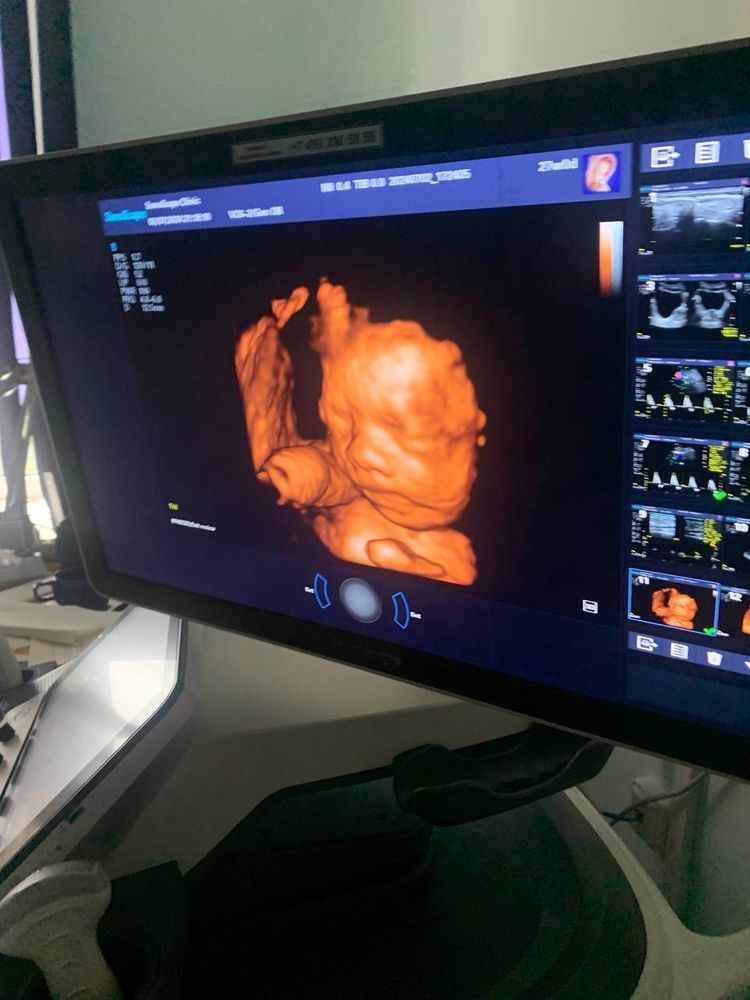

28 неделя 🥰

У меня такой смешной пупок 😂😂😂 жду нашу крошечку, уже мечтаю родить, хотя еще конечно очень рано.